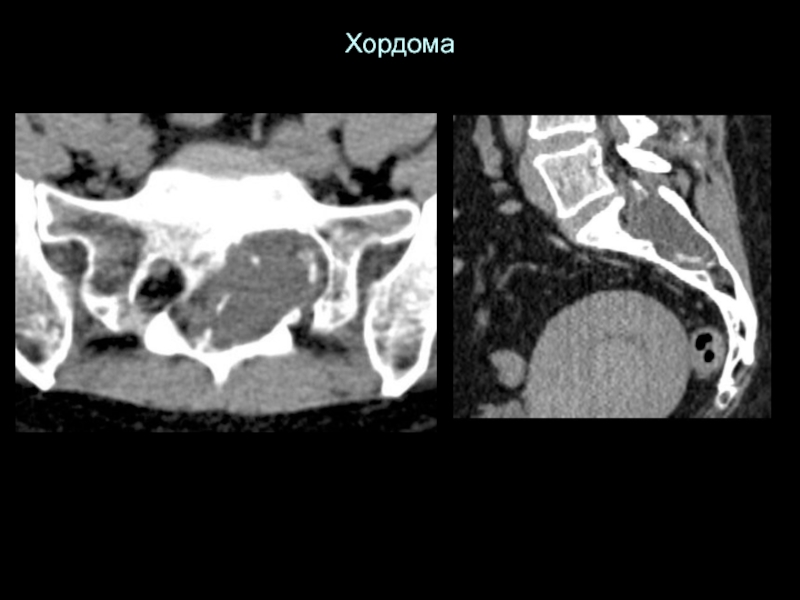

Слайд 32Хордома

Хордома